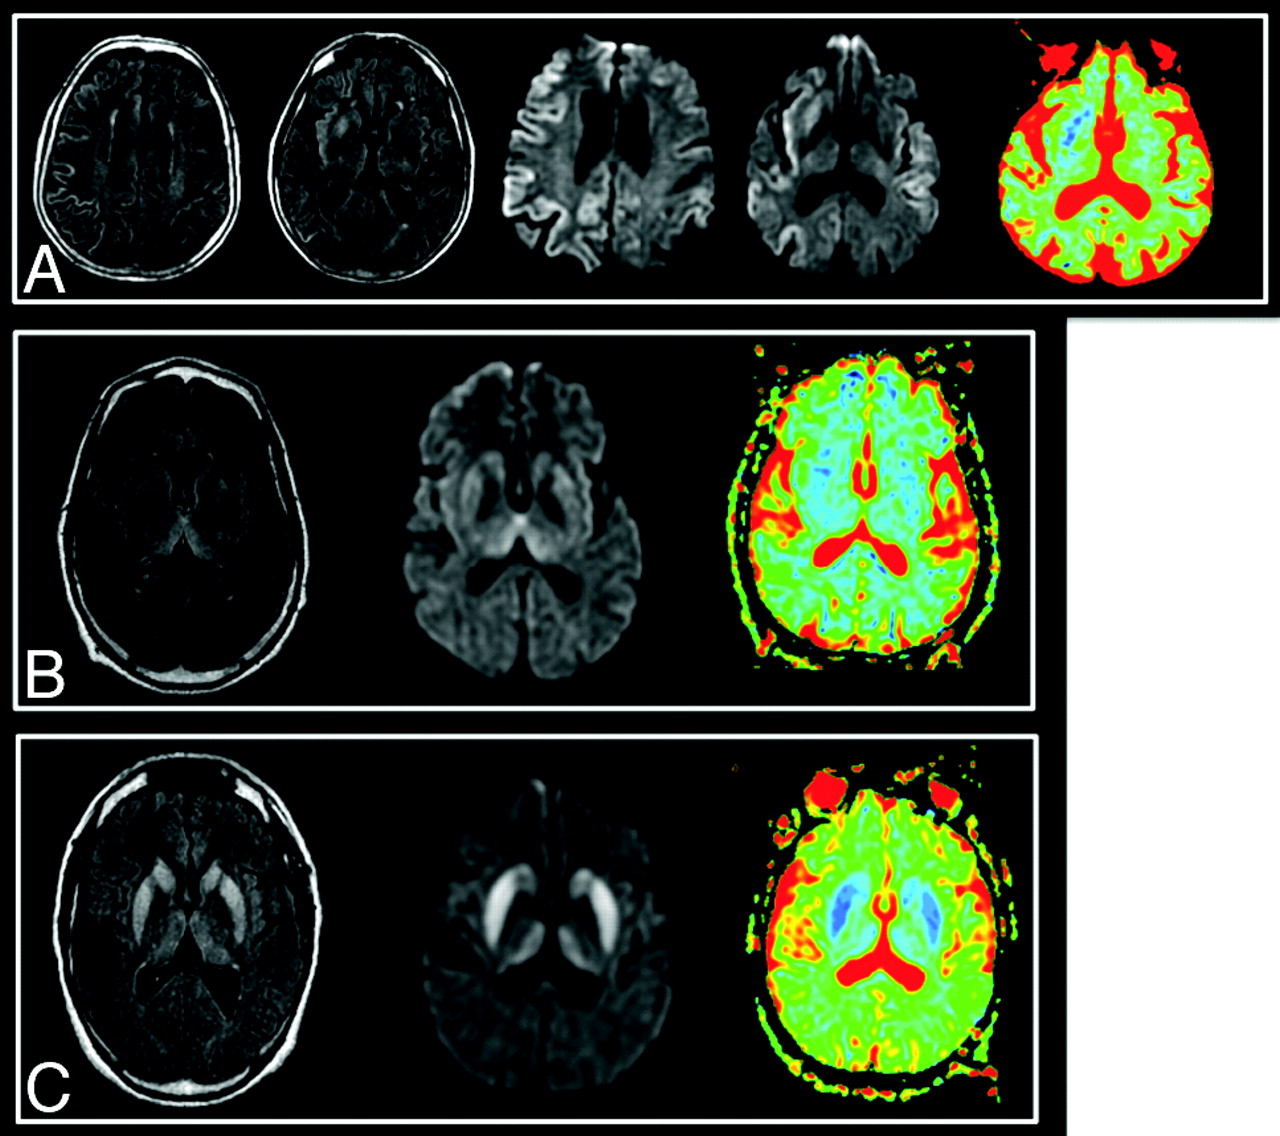

Typical images are shown on Fig 2. The frequency of involvement of the major brain structures is summarized on Table 2.

Typical images in cases of sCJD (A), vCJD (B), and gCJD (C). FLAIR, DWI, and ADC map, respectively, are shown. Areas of increased signal intensity, which involve the cortex and the striatum are more extensive and more clearly visible on diffusion images. On the basal ganglia, these changes are associated with a decreased ADC. There is widespread involvement of the cortex in the patient with sCJD. gCJD and vCJD both present with lesions of the thalamus and lenticular nuclei. However, in the variant case, as opposed to the genetic one, the areas of high signal intensity are more pronounced in the pulvinar than in the striatum as has been previously described in this phenotype.